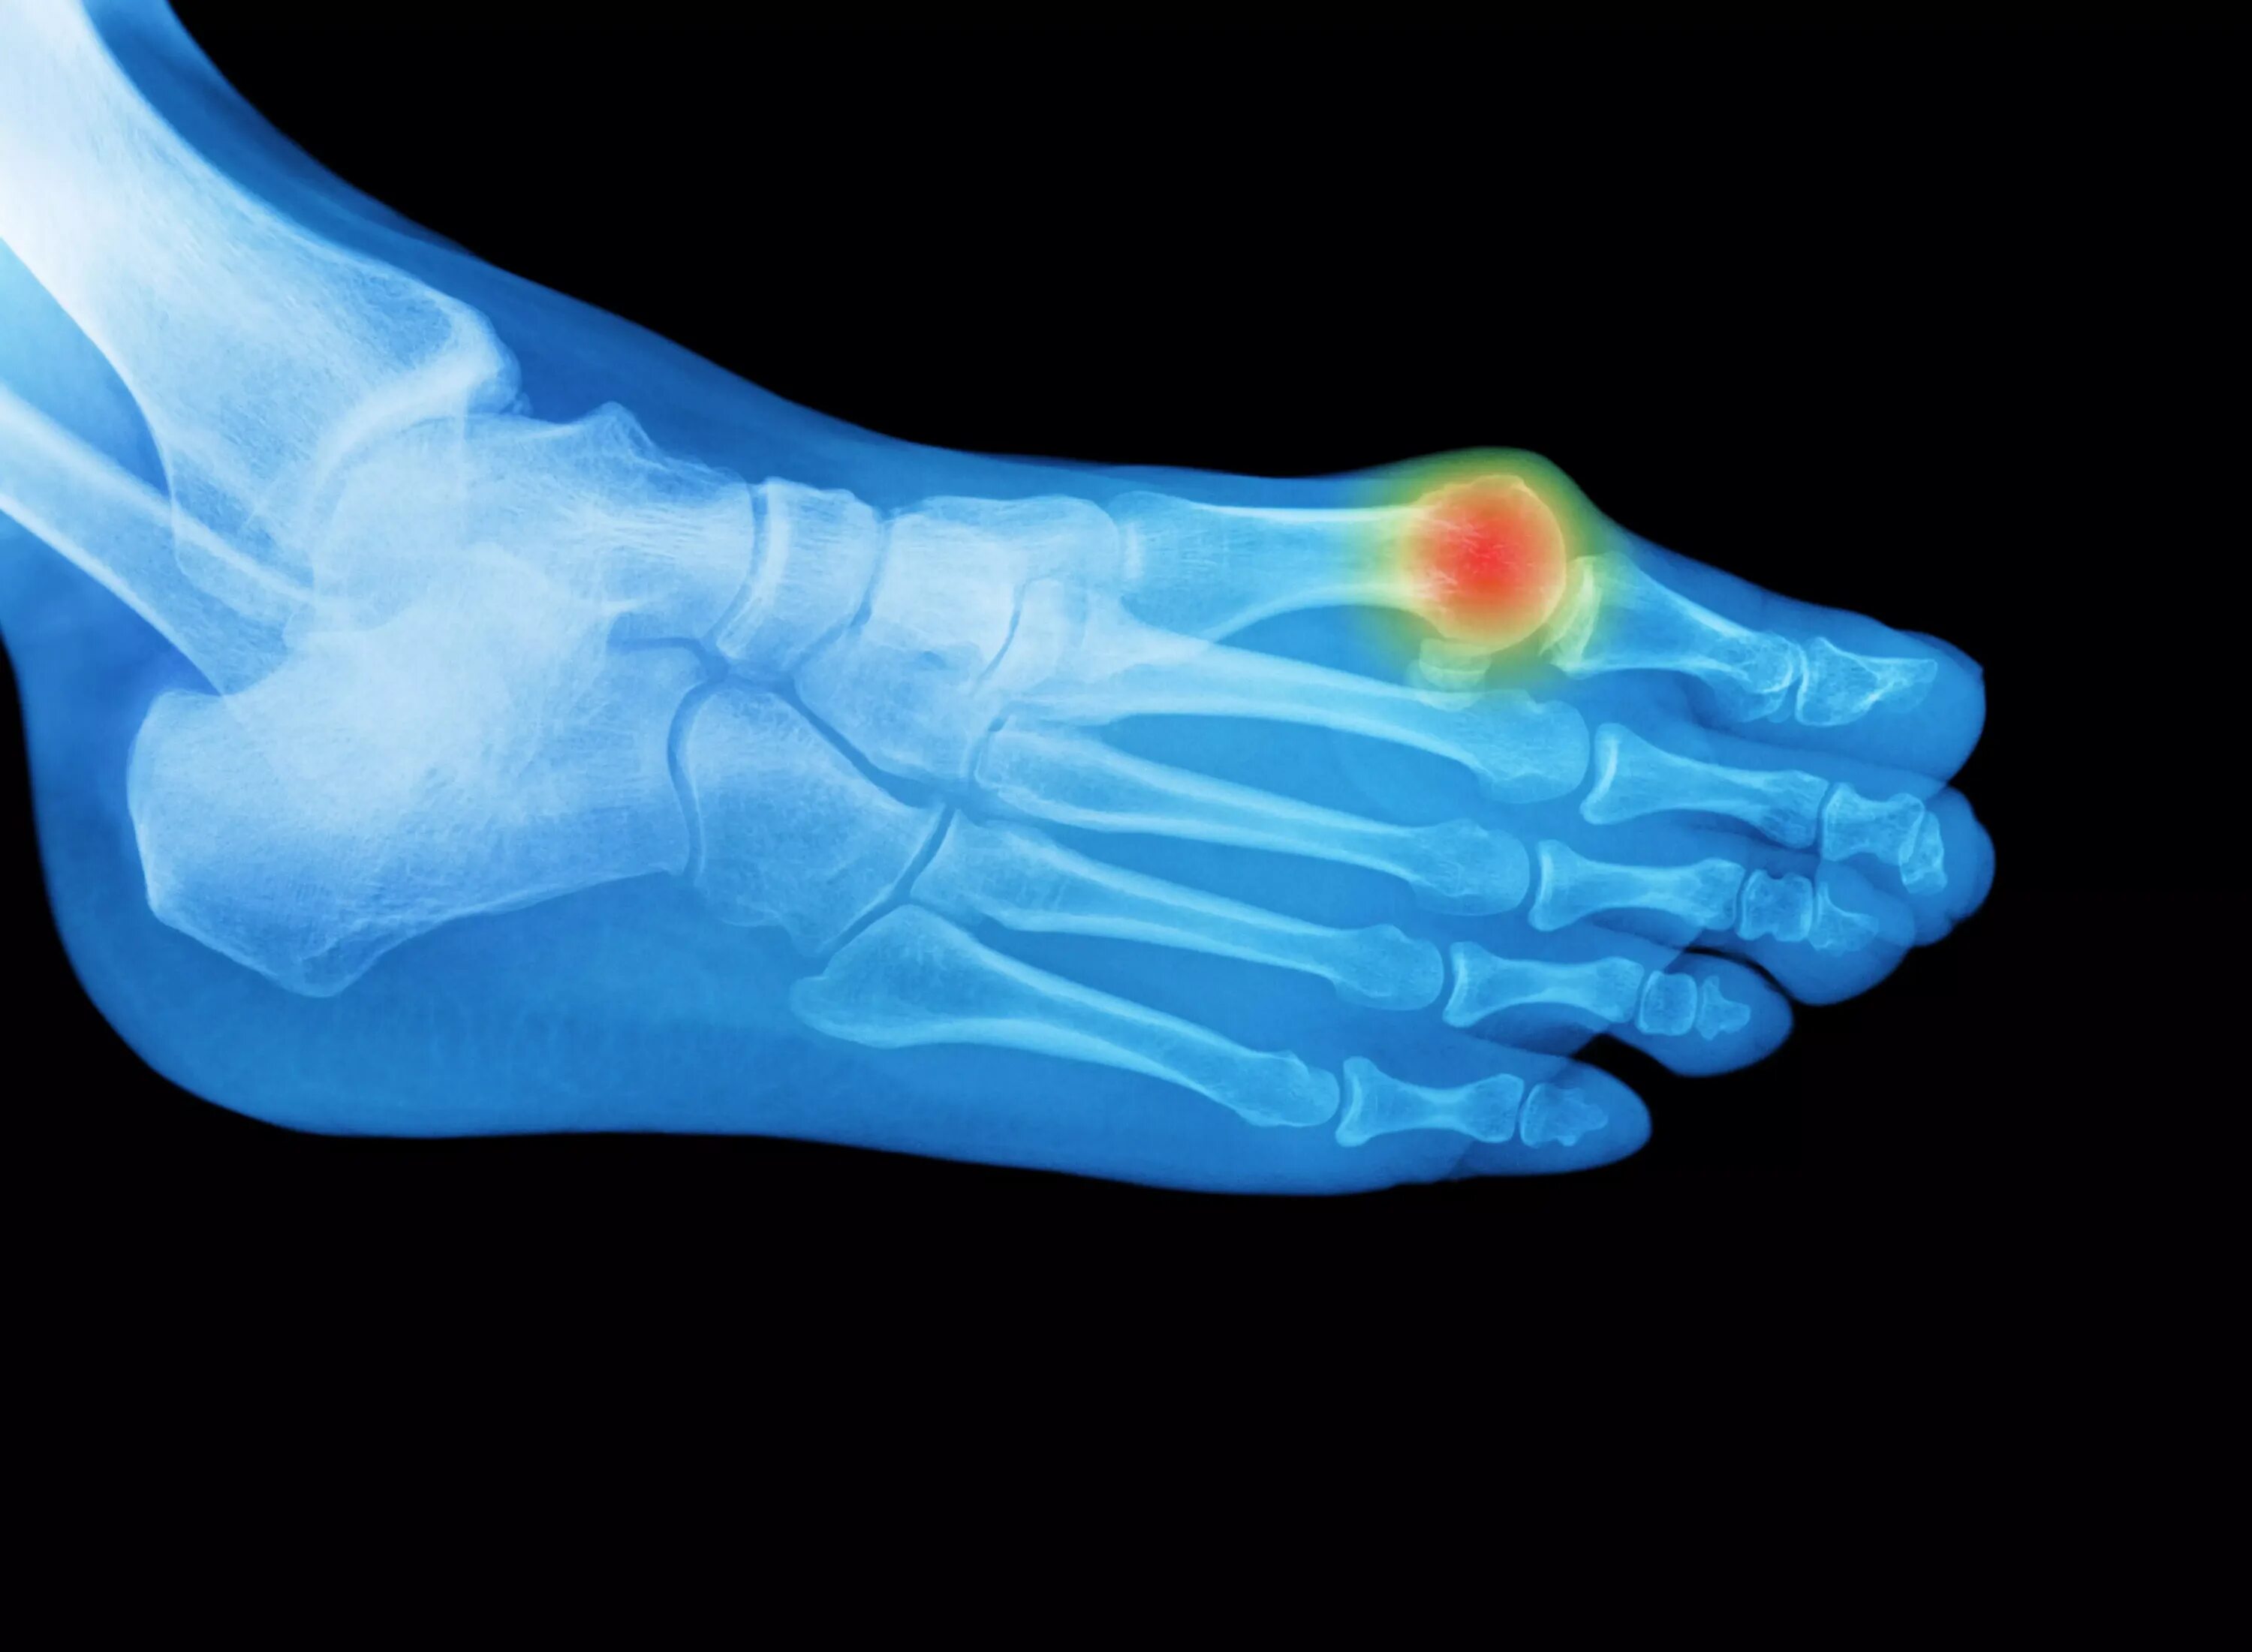

Деформация пальцев стопы мкб